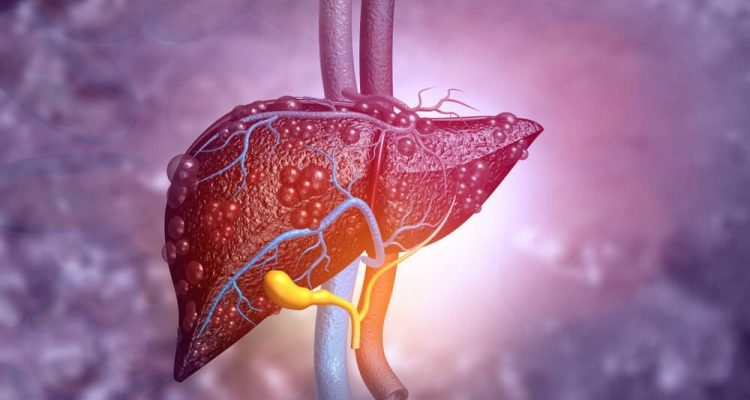

Kepenys atlieka daugybę milijonų gyvybiškai svarbių užduočių per visą gyvenimą, o viena iš svarbiausių – kraujo filtravimas. Viskas, kas patenka į virškinimo traktą, yra apdorojama ir filtruojama per kepenis. Kepenys skaido ir valo chemines medžiagas, riebalus, vaistus, alkoholį ir kitus toksinus iš kraujo, kol jie keliauja po organizmą. Kad ši funkcija būtų atliekama optimaliai, organas turi būti sveikas. O tam svarbu žinoti, kas jam gali pakenkti.